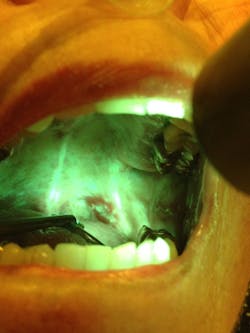

OralID and biopsy to diagnose oral dysplasia

In this study, the author and colleagues identified 53 suspicious lesions (figure 1) in the oral cavity through the use of handheld autofluorescence technology (OralID). The lesions were then sent for biopsy during the period of 2021-2023. The lesions were histochemically stained and sectioned, and graded according to dysplastic progression (figures 2a-2d). Sixty-four percent of the specimens biopsied returned with a grade of mild to moderate epithelial dysplasia or higher.